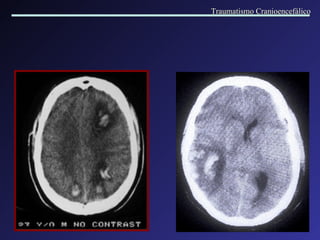

Hematomas subdurais bilaterais, com diferentes idades (crônico à direita e agudo à esquerda), associados a atrofia . Hematomas subdurais bilaterais agudos. Traumatismo Cranioencefálico

Hematoma Subdural Crônico Aparecem 20 dias após o trauma. Mecanismos: transudação de proteínas; hemorragias recorrentes. Variabilidade de manifestações clínicas. Traumatismo Cranioencefálico